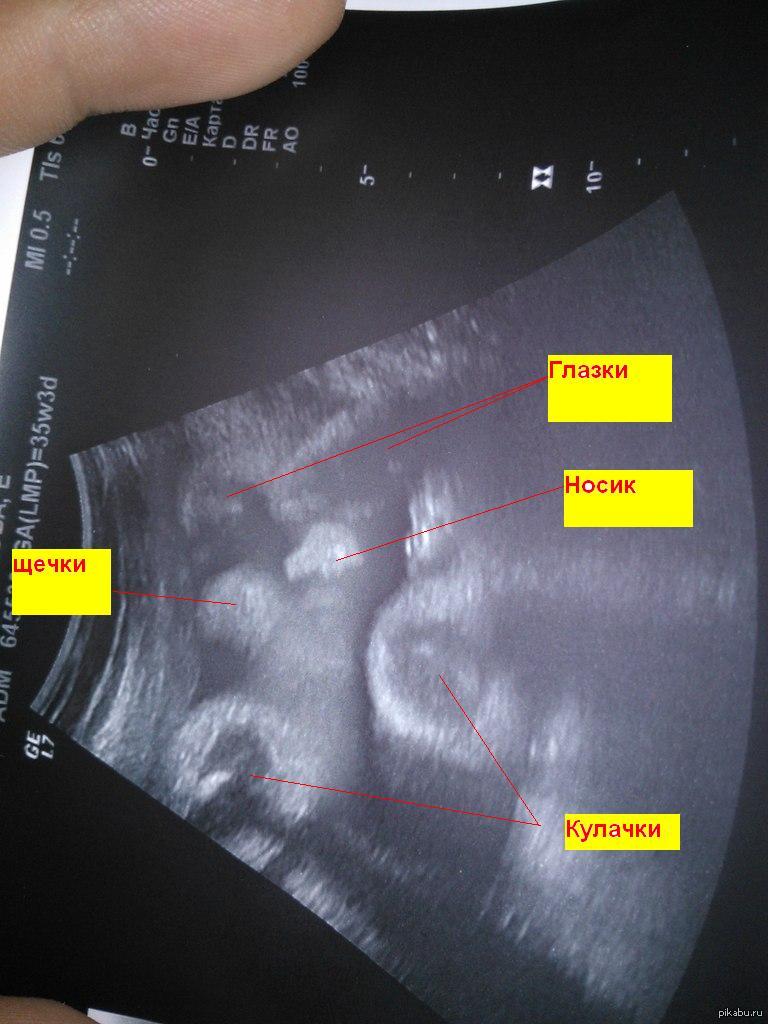

Monolit0ivaN Моя лапость.. 12 лет назад 8 месяцев, 2900..Девочка) [моё] Фотография УЗИ Беременность